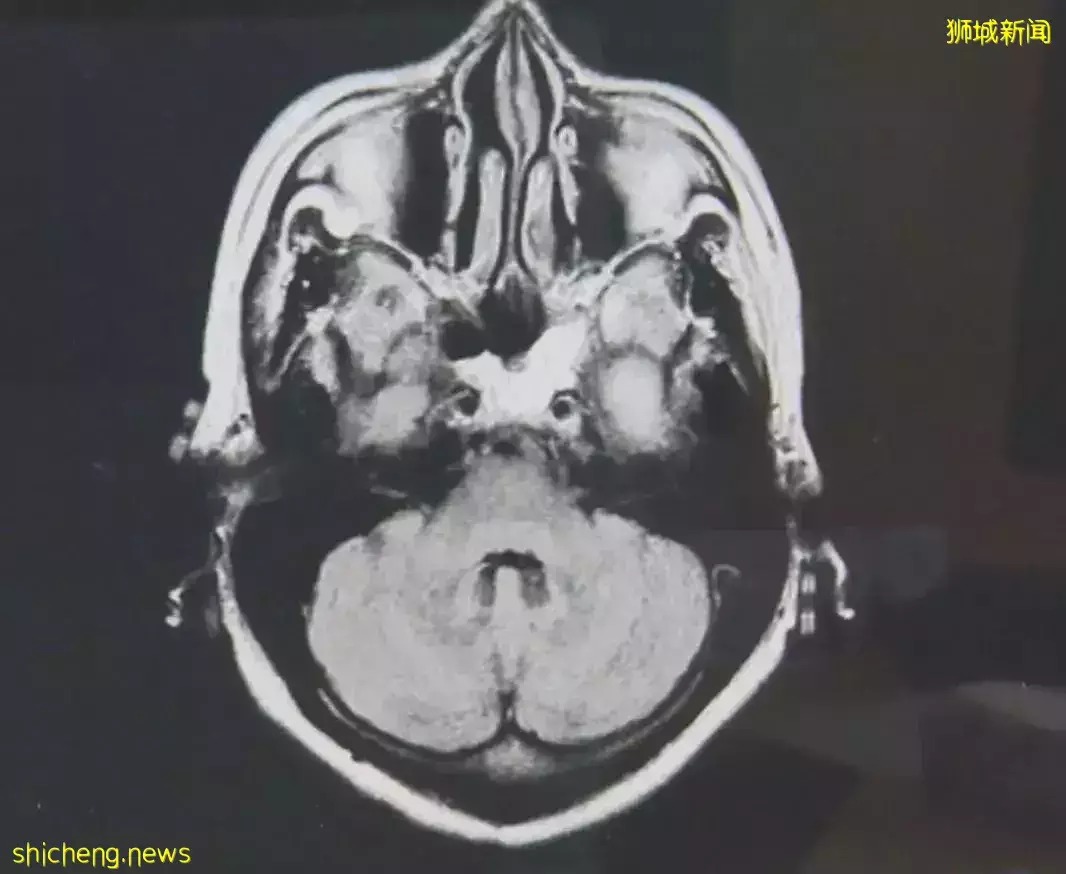

实验照片 研究人员在上述对象的大脑底部嗅球(传递携带气味信息的神经脉冲的部位)中收集组织。

其中,新冠患者嗅球中的轴突量要少得多,且血管损伤程度更严重。但多数新冠患者中的嗅球,没有检测到新冠病毒颗粒。

按照先前的研究,一般人以为没嗅觉的罪魁祸首是新冠病毒碎片残存于鼻腔中。

新冠病毒导致炎症,从而损害神经元,减少可用于向大脑发送信号的轴突数量,并导致嗅球功能失调。